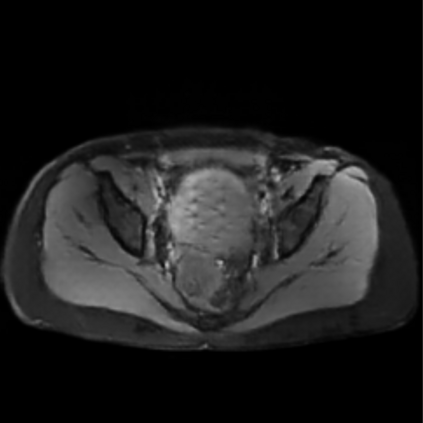

Motion artifacts are a primary source of magnetic resonance (MR) image quality deterioration with strong repercussions on diagnostic performance. Currently, MR motion correction is carried out either prospectively, with the help of motion tracking systems, or retrospectively by mainly utilizing computationally expensive iterative algorithms. In this paper, we utilize a novel adversarial framework, titled MedGAN, for the joint retrospective correction of rigid and non-rigid motion artifacts in different body regions and without the need for a reference image. MedGAN utilizes a unique combination of non-adversarial losses and a novel generator architecture to capture the textures and fine-detailed structures of the desired artifacts-free MR images. Quantitative and qualitative comparisons with other adversarial techniques have illustrated the proposed model's superior performance.

翻译:移动文物是磁共振(MR)图像质量恶化的一个主要来源,对诊断性能产生强烈影响。目前,MR运动的校正要么是预期性的,借助运动跟踪系统,要么是追溯性的,主要是利用成本昂贵的计算迭代算法。在本文中,我们使用名为MedGAN的新颖的对抗性框架,联合追溯性地校正不同身体区域的硬性和非硬性运动文物,而不需要参考图像。 MedGAN利用非对抗性损失和新型生成器结构的独特组合来捕捉无MR图象的纹理和精细详细结构。 与其他对抗性技术的定量和定性比较展示了拟议模型的优异性表现。